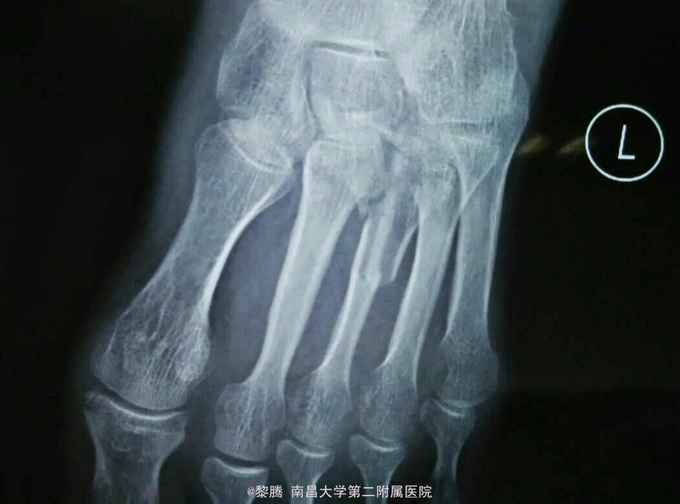

外伤致左足肿痛,活动受限6小时 患者老年女性,因外伤砸中左足,致左足出现明显肿痛,伤后当即出现左足活动受限,患者伤后急诊入我院就诊行左足正斜位片提示左侧跖骨骨折,随后收入住院进一步治疗。

查体:左足肿胀明显,局部皮肤可见明显青紫及张力性水泡,左足背动脉搏动存在,左足各趾感觉无明显异常,肢体末梢血运可 辅查:左足正斜位片提示左第3跖骨骨折。

诊断:左足第3跖骨骨折 治疗:骨折切开复位内固定